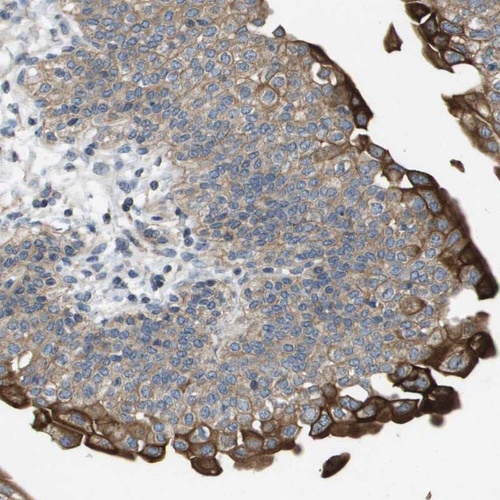

Immunohistochemical staining of human urinary bladder shows strong cytoplasmic positivity in a subset of urothelial cells.